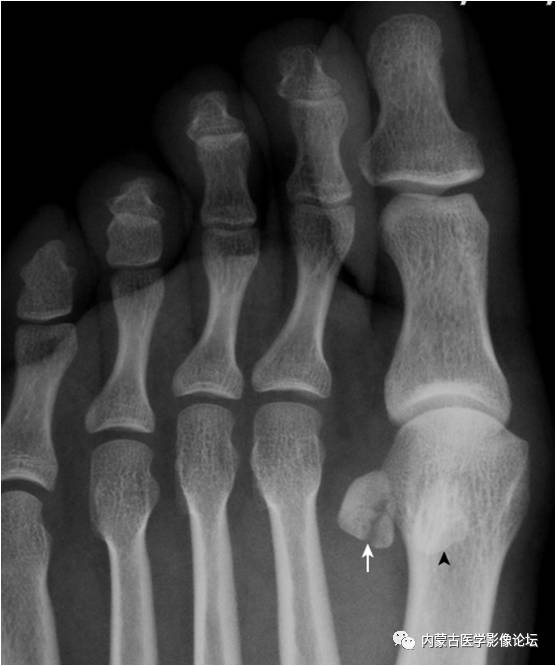

19.拇趾多分籽骨:拇趾内外侧籽骨可表现为二分籽骨(箭)或三分籽骨(箭头),为正常变异,需与籽骨骨折、坏死鉴别。骨折边缘多不规则,坏死密度多不均。

21.足趾副骨:趾跖关节内侧见点状骨性灶(箭),又称关节旁骨,一般无病理意义,但有时可引起邻近骨生长障碍和坏死。要与撕脱骨折鉴别。

32.拇趾撕脱骨折:该例为陈旧性撕脱骨折。拇趾外侧基底部部分撕脱,虽游离骨片(箭)边缘清晰,但与基底部有很好的对合,可与关节旁骨相鉴别。